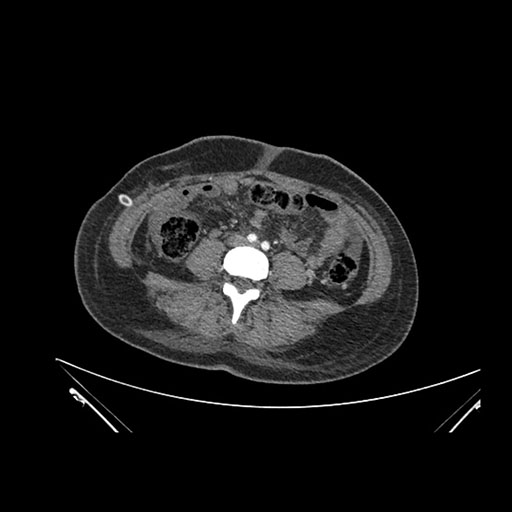

Axial Arterial

Axial Venous